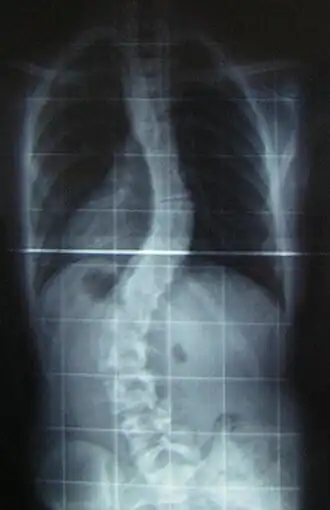

Величина искривления позвоночника измеряется с помощью рентгеновского снимка всего позвоночника стоя. Возможны и врождённые рёберные деформации и деформации тел позвонков. С помощью этой информации можно отличить идиопатический и врождённый сколиоз. На рентгеновском снимке в боковой проекции можно также определить, есть ли врождённые деформации в этой плоскости или нарушения нормальных изгибов позвоночника — физиологических кифозов и лордозов.

Схема анализа рентгеновского снимка для определения угла искривления разработана в 50-х годах XX века американским ортопедом Дж. Коббом (англ. John Robert Cobb). Угол искривления, измеренный по рентгеновским снимкам теперь называется «углом по Коббу». Для определения угла деформации на передне-задней рентгенограмме проводят две линии, параллельных замыкательным пластинкам нейтральных позвонков. В точке пересечения этих линий или перпендикуляров к ним измеряют угол сколиоза.

При оперативном лечении искривлённая часть позвоночника выпрямляется до определённого возможного угла при помощи металлических стержней и шурупов (т. н. транспедикулярных винтов), что ведёт к полному обездвиживанию этих отделов позвоночника. Операция при сколиозе подходит прежде всего для сильных искривлений, которые больше не могут лечиться другими методами. Оперативная фиксация может предотвратить дальнейшую прогрессию и ухудшение состояния.